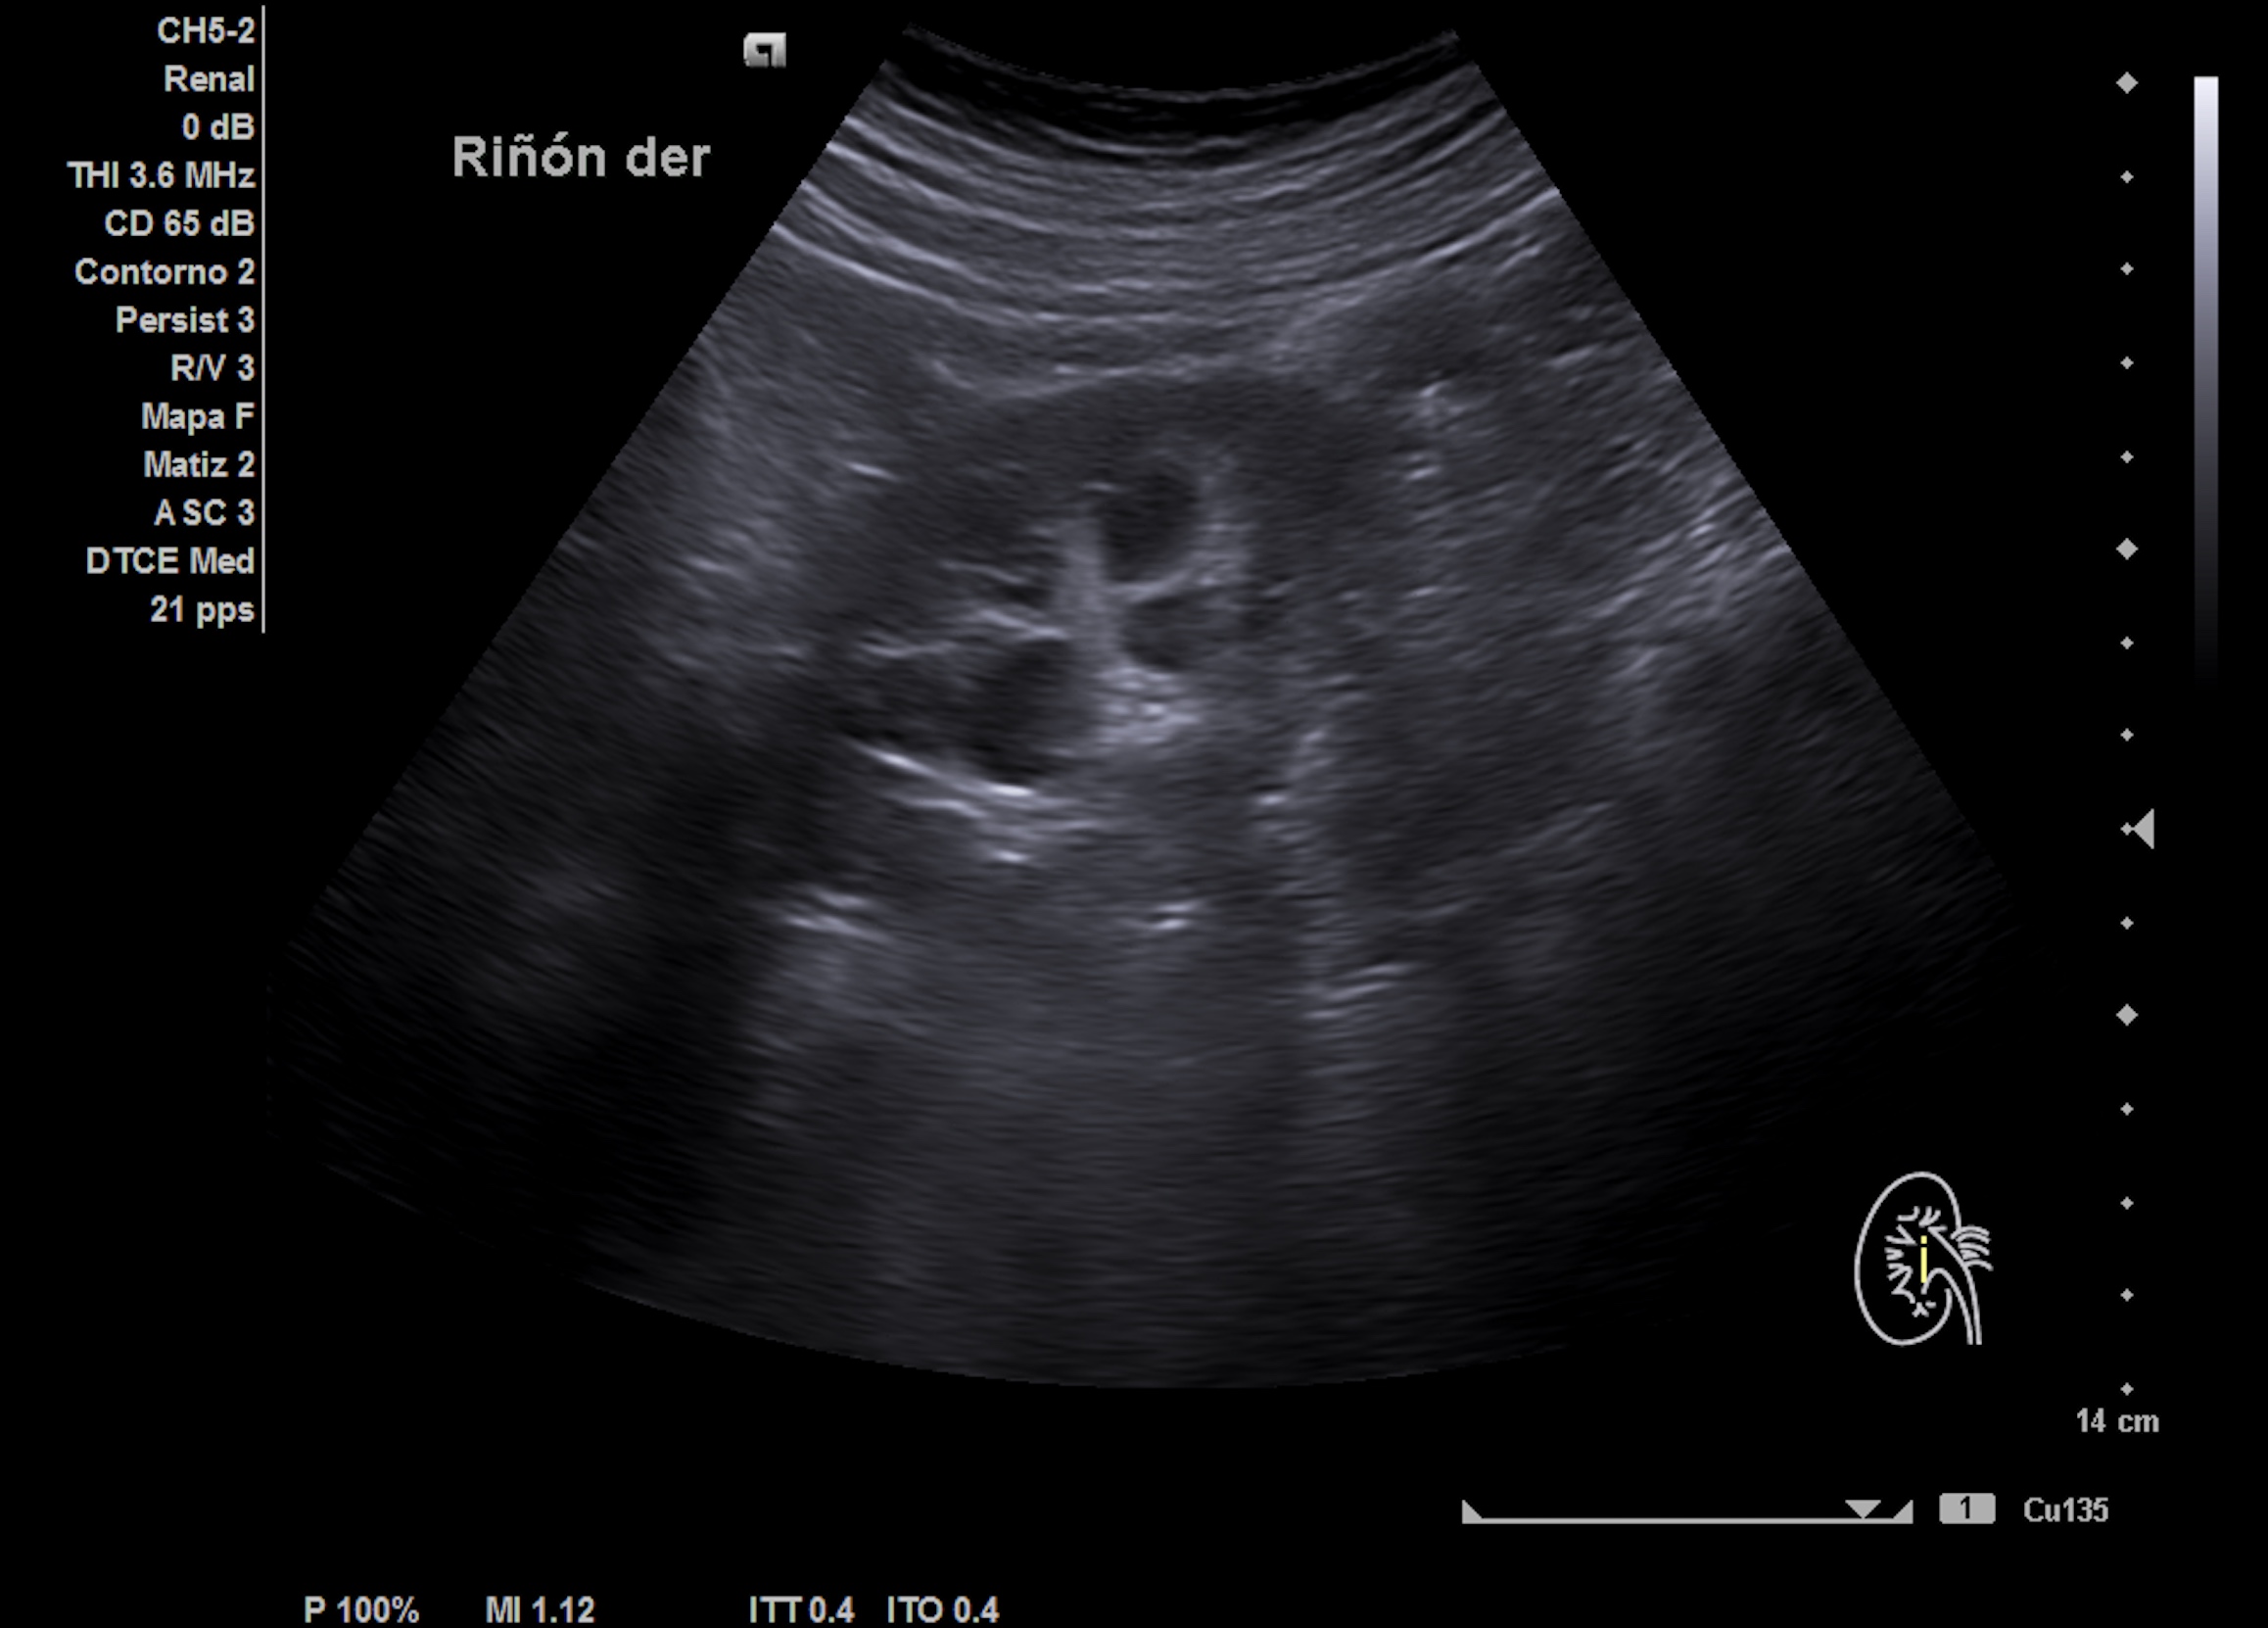

Mujer de 53 años que consulta por dolor abdominal en flanco derecho irradiado a región inguinal y fosa lumbar ipsilateral desde 1 semana, afebril y hematuria franca actual. Ante la persistencia de episodios de dolor en flanco dcho que irradia hacia zona renal dcha y algo a FID, sin expulsión de cálculos urinarios se repite la ecografía.

Ecografía clínica abdominal 1ª: hígado de ecoestructura y tamaño normal. Vesícula biliar alitiásica. Riñón derecho con quiste simple en polo inferior de 2,5 cm conocido previamente. No nefrolitiasis ni hidronefrosis con jet ureteral bilateral normales.

Nueva ecografía clínica renal, vías urinarias y vejiga (a la semana): hidronefrosis grado II que no presentaba hace 1 semana, no nefrolitiasis en cálices renales. Jet ureteral dcho permeable, en zona intermedia de uréter dcho presenta cálculo de 8 mm enclavado en el cruce de los vasos ilíacos con uréter.